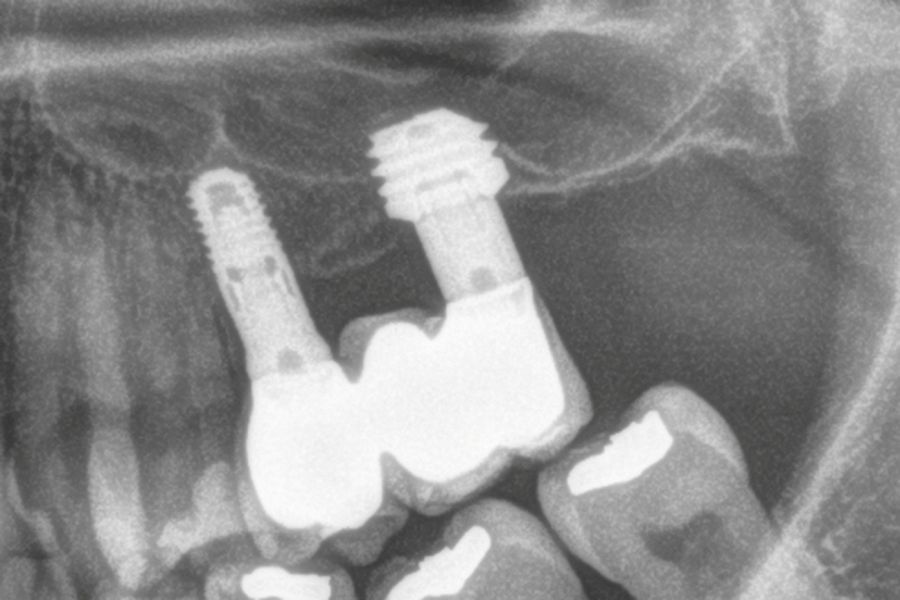

En las Figuras 7- 13 se muestra uno de los casos incluidos en el estudio.